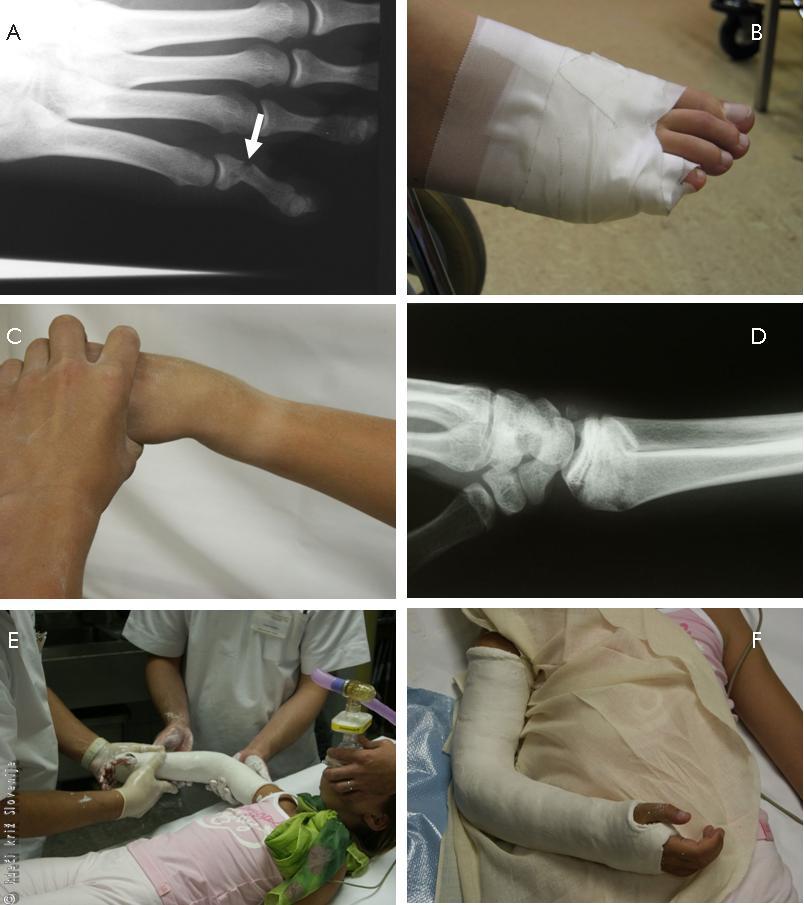

Slika 8

A – Nepravilna oblika zapestja.

B – RTG znaki zloma koželjnice na značilnem mestu.

Slika 17

A – RTG slika ki pokaže zlom osnovnega členka mezinca desne noge(puščica).

B – Obližna imobilizacija k sosednjemu prstu.

C – Spremenjena oblika podlahti pri zlomu.

D – RTG slika, ki pokaže zlom koželjnice.

E – Naravnava in zamavčenje v splošni anesteziji.

F – Doramenski mavec.

Naravnava in zamavčenje zloma podlahti pri otroku v splošni anesteziji.